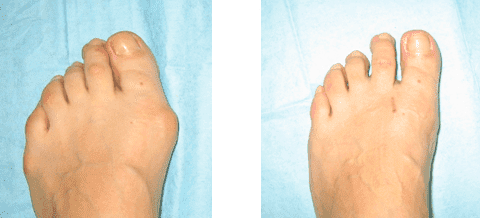

Astăzi am să vă spun cum am scăpat de un nod de la degetul mare. A trebuit să suport cea mai dificilă operație și cele mai grave consecințe după ea și am scăpat de osul proeminent cu o simplă asociere

Piciorul meu la 1 lună după operație

Raze X ale picioarelor înainte și după tratament

Piciorul meu la o lună după operație

Picioarele mele la o lună după operație

Picioarele mele la 9 luni după operație

Așa arată picioarele mele la un an după ce am folosit FORTU FLEX